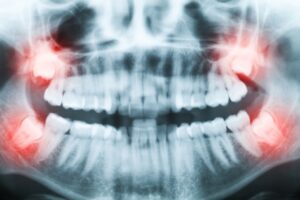

Read More5 Things To Know About Wisdom Teeth Extractions

January 4, 2023

Having your wisdom teeth removed is a common procedure in the dental world. Each patient reacts differently to wisdom teeth extractions and anesthesia which may cause some anxiety. Mountain View Dental wants to help patients know what each dental procedure will entail and provide peace of mind. When you need a wisdom tooth extraction here are all the things you need to know before going in.